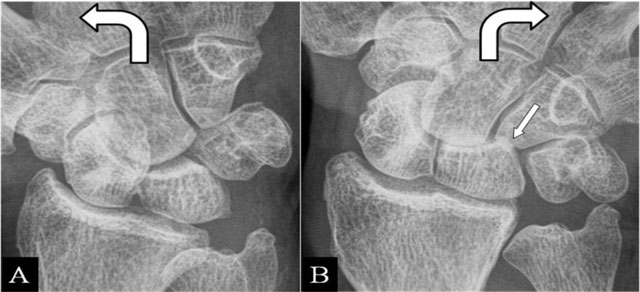

Figure 6

(Intra)scaphoid abutment. (A, B) PA plain mobility radiographs in ulnar and radial deviation. (A) Large diastasis in ulnar deviation between the scaphoid bone fragments. (B) Impaction of both fragments in radial deviation. Associated midcarpal osteoarthritis (arrow).